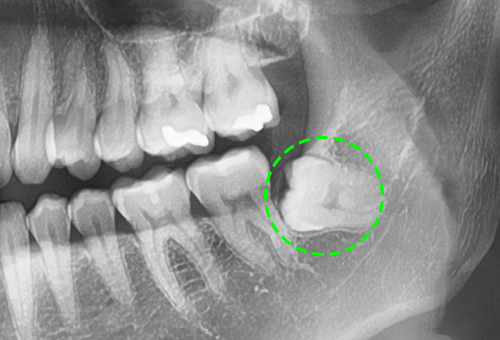

• 누워서 가로로 자란 사랑니

주변치아의 충치와 염증을 유발하기 쉽고, 턱뼈에 압력을 가해 지속적인 통증을 유발하거나,

턱뼈가 약해질 수 있습니다.